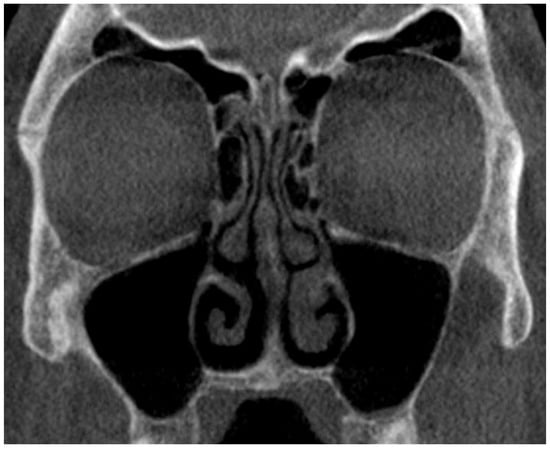

3.4. Image Quality

A representative CBCT image from our clinic is shown in Figure 1. One of the twenty patients (5%) in the CBCT group treated surgically underwent further FBCT after the CBCT images were considered inadequate by the treating Surgeon.

Figure 1. A representative CBCT image from our clinic.